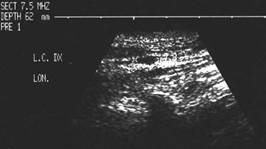

Lob drept , proiectie longitudinala si trasversala .

Barbat de 44 ani. Nodul mare in lobul drept si istm de 31x44x44mm, (30 cc) cu contur net, hipoecogen, neomogen, cu macrocalcificare.

Examn citologic: neoplazie oncocitara (a c. Hurthle).

Examen histologic postoperator: adenom cu celule Hurthle.